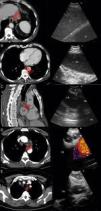

Histological biopsies obtained by mediastinoscopy have been the diagnostic gold standard for a long time but this surgical approach is invasive and associated with morbidity and additional costs.11,12 Therefore, minimally invasive techniques have been developed. EUS-NA, the endoscopic sampling of cytological specimens from the mediastinum through the esophagus, is the older technique, largely performed by gastroenterologists. With the EUS-scope the left mediastinum and the upper part of the abdomen can be assessed. In contrast, EBUS provides an endoscopic access to the upper mediastinal and the hilar lymph node stations, but distal paraesophageal lymph nodes or structures below the diaphragm cannot be reached via the endobronchial way. Both techniques represent a valuable alternative to surgical staging (Fig. 1).

a) 56-year-old patient with a PET-positive pulmonary tumor in the left upper lobe suspicious of primary lung cancer (TU). In lymph node station 7 (LN7) there is increased FDG-uptake; (b) EBUS image of the lymph node in station 7; (c) corresponding EUS-B image of the same lymph node from esophagus with the same bronchoscope; (d) cytological image of the EUS-B-NA showing adenocarcinoma cells with background blood (courtesy of Cynthia van der Horst, MD, Glasgow, UK).

The accuracy of EUS-NA and EBUS-TBNA for evaluating mediastinal lymph node metastasis has been assessed in several clinical trials. In meta-analyses concerning this indication, the pooled sensitivity for EBUS-TBNA was 93%, whereas a sensitivity of 83% for EUS-NA was reported.13,14 Furthermore, in numerous studies it has been shown that the diagnostic value of a combined EBUS/EUS procedure was superior to either EBUS-TBNA or EUS-NA techniques alone, but no randomized controlled trials comparing these attempts had been performed yet 4.15,16

As previously mentioned, in two studies published simultaneously, both EBUS-TBNA and EUS-B-NA were performed in patients with suspected lung cancer for diagnosing and staging.4,5 The sensitivity for EBUS-TBNA was 91.5% and 84.4% respectively. Sensitivity for EUS-B-NA alone was 88.7% in one trial. For the combined approach of EBUS-TBNA plus EUS-B-NA the sensitivity rose to more than 90% in both trials. Importantly, the negative predictive value for malignancy using combination of EBUS and EUS-B was 96% in both trials. Particularly high negative predictive value for malignancy may in the future reduce the need for surgical confirmation, when the results of the needle acquired specimens are negative for malignant cells.